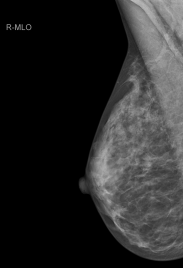

Mamografía

En qué consiste una mamografía

La mamografía es un tipo específico de imágenes que utiliza un sistema de dosis baja de rayos X para examinar las mamas. Un examen de mamografía, llamado mamograma, se utiliza para asistir en la detección temprana y el diagnóstico de las enfermedades mamarias en las mujeres.

Cómo se realiza

Durante la mamografía, un técnico de radiodiagnóstico cualificado posicionará su mama en la unidad de mamografía. La mama será colocada en una plataforma especial y comprimida con una paleta (por lo general hecha de Plexiglás transparente u otro plástico). El técnico comprimirá la mama gradualmente y realizara el estudio.